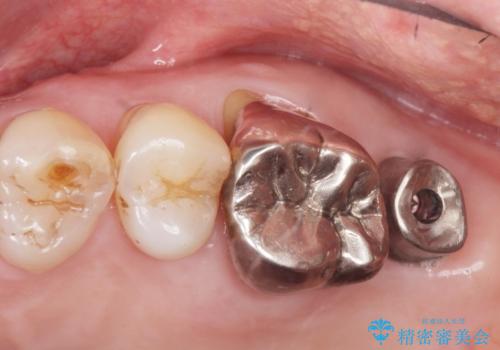

奥歯でしっかりと咬むことができるようになり、ご満足頂けました。

初診時から治療終了時までのレントゲンをお見せして説明差し上げたところ、「お~!骨ができている!」と喜んで下さいました。

ソケットリフトにより上顎洞底を挙上し骨造成することにより、骨の厚みが薄い部分でもインプラントが可能になります。

インプラントの種類:ストローマン BLT

クラウンの種類:メタルボンドクラウン エコノミー